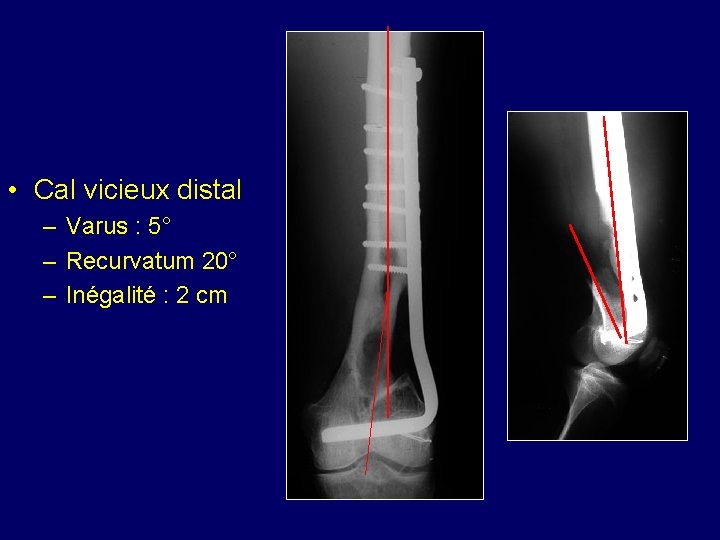

• Cal vicieux distal – Varus : 5° – Recurvatum 20° – Inégalité : 2 cm

Ostéotomie et utilisation d’une plaque spéciale conçue pour intégrer la correction en utilisant les mêmes trous que l’ancienne Le recurvatum est corrigé